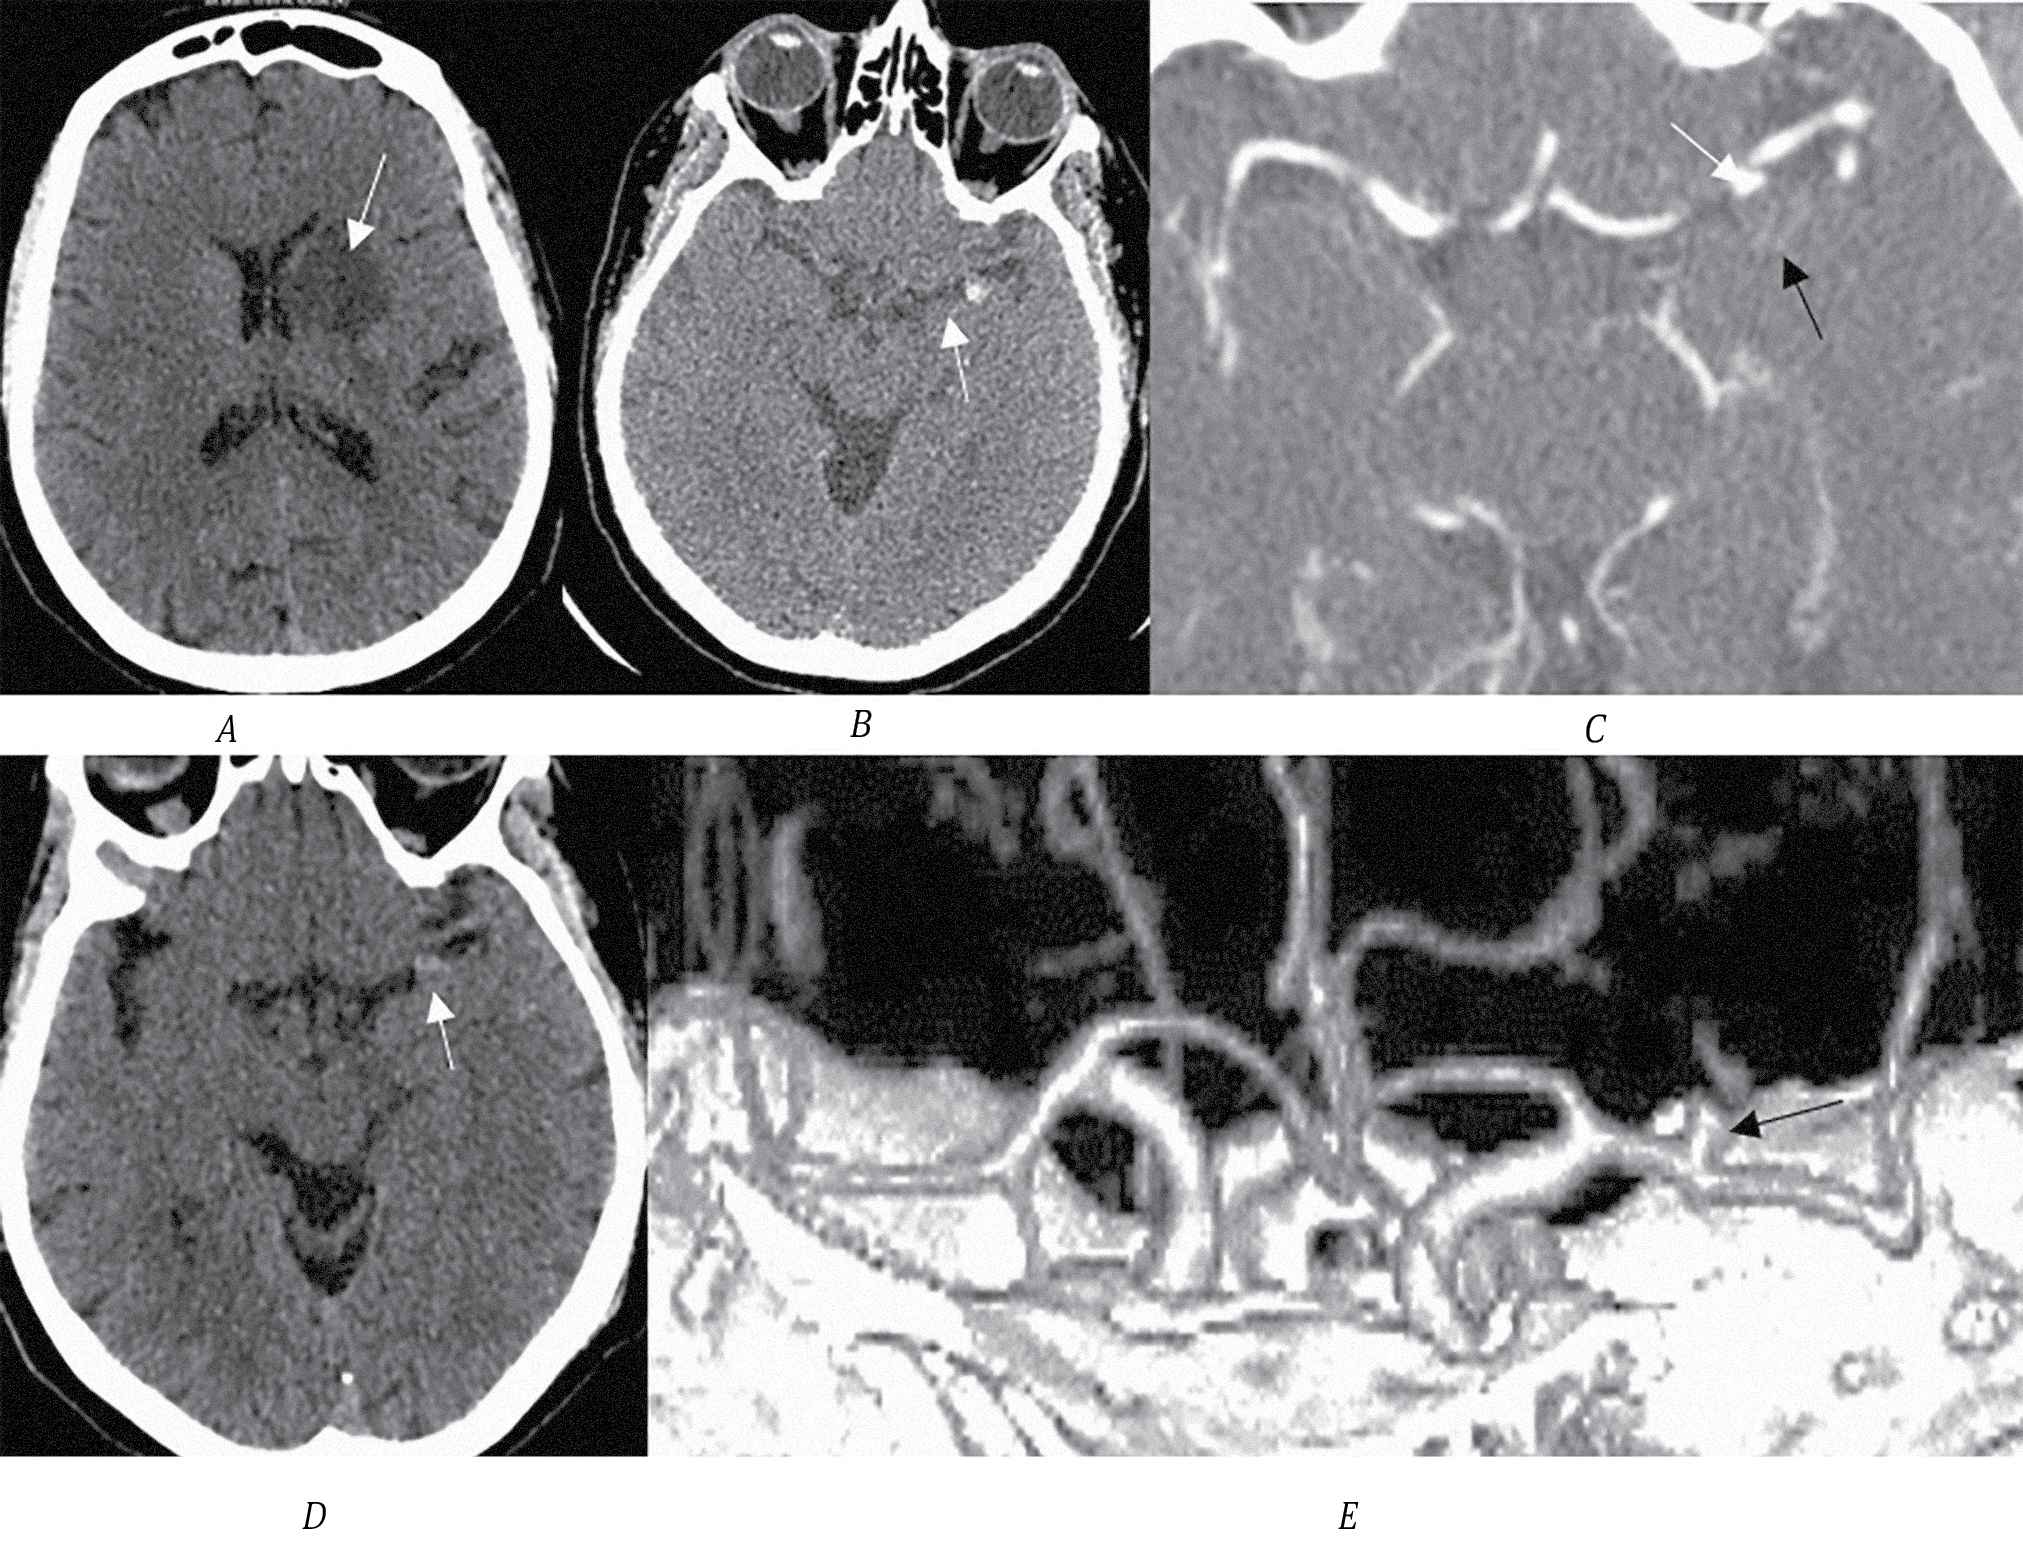

Пациентка Б., 57 лет, поступила в первичное сосудистое отделение с клиникой глубокого правостороннего гемипареза (до 3 баллов в руке и ноге). Неврологический дефицит тяжёлой степени (14 баллов по NIHSS). По данным МСКТ определена зона ишемии в области скорлупы, внутренней капсулы и головки хвостатого ядра слева (рис. 1, А). Обращает на себя внимание гиперденсный участок в области сильвиевой щели, который необходимо дифференцировать с кровоизлиянием и ТА (рис. 1, B). По МСКТ-ангиографии выявлена функционирующая часть ТА М1-сегмента СМА (рис. 1, C). Через 3 мес пациентка поступила на плановое оперативное лечение по поводу аневризмы СМА. В динамике на нативном МСКТ-исследовании сигнал от аневризмы стал изоденсным, по МСКТ-ангиографии определяется функционирующая часть аневризмы размером до 3,5 мм (рис. 1, D, E).

Рис. 1. МСКТ головного мозга пациентки Б.

А — острая ишемия в области головки хвостатого ядра, внутренней капсулы и скорлупы (стрелка); B — тромбированная часть аневризмы (стрелка); C — функционирующая часть аневризмы (белая стрелка), чёрной стрелкой указаны контуры тромбированной части; D — МСКТ пациентки через 3 мес после инсульта, стрелкой указана тромбированная часть аневризмы; E — 3D-реконструкция функционирующей части аневризмы (стрелка).

В остром периоде ИИ тромбированная часть аневризмы имела яркий (гиперденсный) сигнал, что указывает на наличие свежего тромба (рис. 1, B), а через 3 мес сигнал от тромба стал изоденсным (рис. 1, D). На основании зон ишемии в бассейне кровоснабжения лентикулостриарных ветвей и наличия свежего тромба в аневризме можно предположить, что причиной развития ишемии стал тромбоз стриарных ветвей СМА эмболом из мешка аневризмы. Других факторов риска ИИ у пациентки не выявлено. Выполнено микрохирургическое клипирование аневризмы. На операции определены небольшая функционирующая часть аневризмы и крупная тромбированная часть (13 мм). Мешок вскрыт, тромбы удалены, на сформировавшуюся шейку наложен постоянный клипс. Пациентка выписана с дооперационным функциональным статусом с оценкой по модифицированной шкале Рэнкина 3.